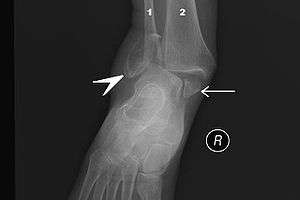

|

Bimalleolar fracture and right ankle dislocation on X-ray (anteroposterior). Both the end of the fibula (1) and the tibia (2) are broken and the malleolar fragments (arrow: medial malleolus, arrowhead: lateral malleolus) are displaced. | |